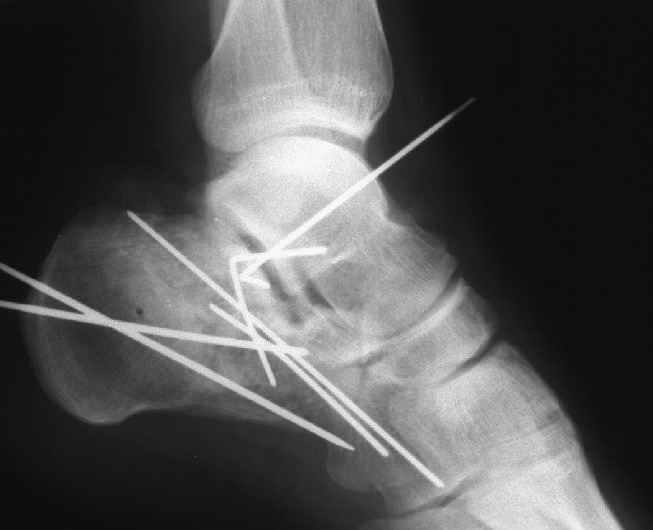

Накладываем спицевой дистрактор, позволяющий выхаживать м/ткани и одновременно устранять захождение отломков.